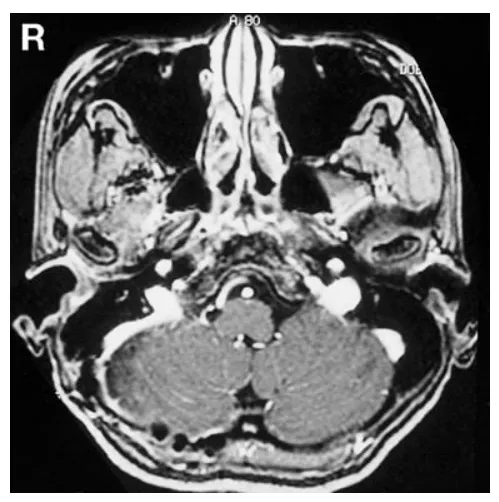

幸运的是,小葵在出院前实用听力已恢复。术后1周纯音听阈测定证实其听力恢复(图2右)。术后8个月磁共振成像复查未见肿瘤复发(图3)。

图3术后8个月轴位增强T1加权磁共振成像显示,肿瘤无复发。